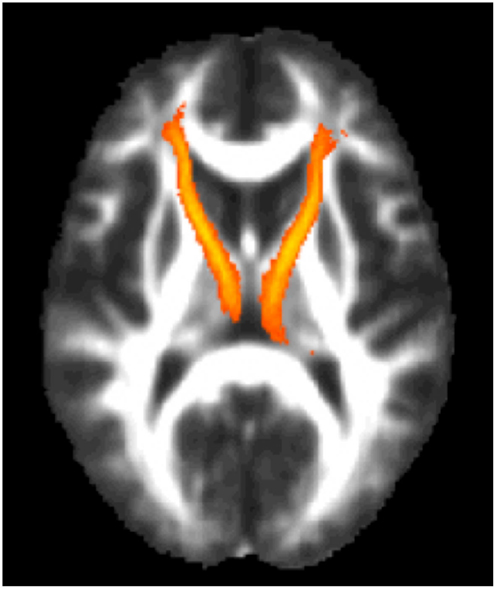

Given the study hypothesis, regions of interests (ROIs) were created for the left and right ATR utilizing the JHU white matter tractography atlas (61, 62). The left and right ATR ROIs were thresholded to minimum of 25 and maximum of 100 to obtain 75% probability of the ROI being within the ATR bundle (See Figure 2). After thresholding, the left and right ATR ROIs were utilized to extract mean FA values for each participant. Next, the left and right ATR were combined and used as a white matter mask and voxel-wise group comparisons were performed via permutation testing in randomize, within FSL. The Threshold-Free Cluster Enhancement option in Randomize was used to eliminate the need to estimate a cluster-forming threshold and 5000 permutations were run for each group comparison and for each regression analysis. Test-statistical maps were produced for group and regression analyses and voxels with a p ≤ 0.01 were considered significant. The TBSS_fill command was used within FSL to improve visualization of voxels that were significant.

FIGURE 2

www.frontiersin.org

Figure 2. The region of interest/mask of the bilateral anterior thalamic radiations shown in yellow-orange superimposed on the group mean fractional anisotropy image for the entire cohort. The region of interest/mask was thresholded to a 75% probability of being within the actual anterior thalamic radiations.